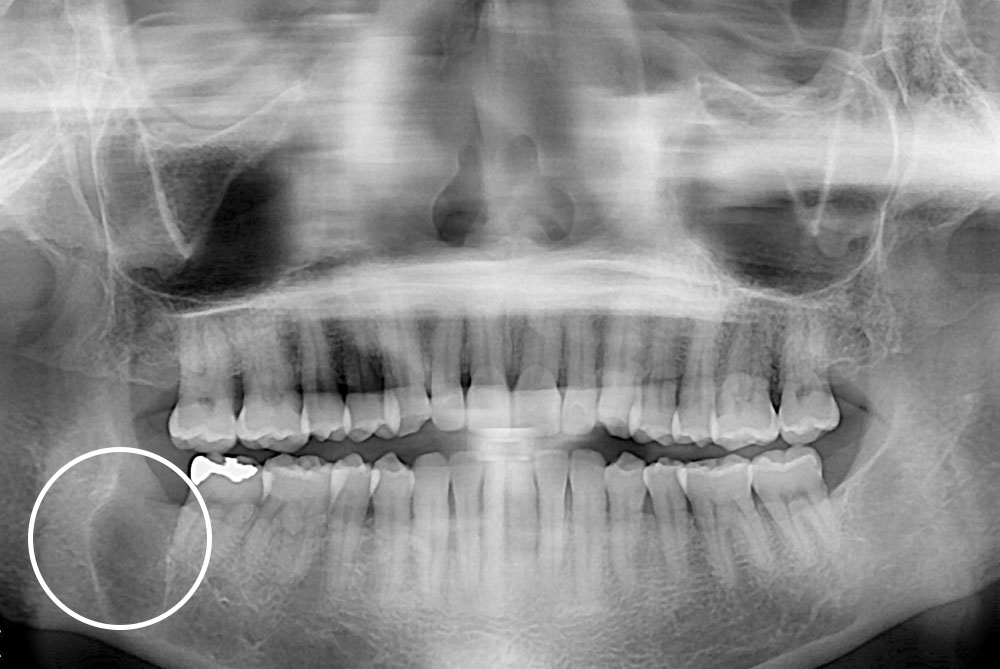

[사랑니] 매복 사랑니 발치

치료전 : 2017-03-07